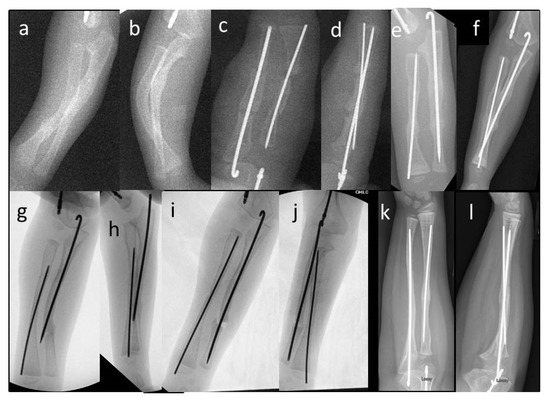

The indication for surgery in all children was deformity with recurrent fracture and loss of motion interfering with function (Figure 1). Surgical treatment of the forearm bones was discussed with families when the children were experiencing multiple radius and/or ulna fractures that resulted in bowing of the forearm that resulted in difficulties with function. All surgeries were performed by the senior author. Forty-eight total bony procedures on 18 patients were performed with 9 patients having only one forearm corrected and 9 having both forearms corrected. In total, 29 total procedures were performed on the right (14 forearms) and 19 total procedures on the left (13 forearms). Fourteen patients are right-hand dominant, 1 is left-hand dominant, and 3 do not have hand dominance recorded in the chart. Bilateral forearm surgery was performed in separate operative trips for all except one patient whose mother requested that we treat both forearms in the same operative setting. If there were recent fractures, we attempted to percutaneously pass a k-wire in the radius or ulna as we manually corrected the deformity. If this was deemed unsafe, or if an osteotomy was needed to correct the deformity, we opened at the apex of the deformity and attempted to perform one osteotomy. We routinely performed this with a rongeur, passing a separate wire into the next segment before passing the wire across the osteotomy site. If the deformity could not be corrected fully we performed a second osteotomy. The ulnar wire was placed across the olecranon apophysis to protect the entire ulna down to the distal ulnar physis. The radial wire was placed through the radial styloid across the distal radial physis up to the proximal radial physis to protect the entire radius. The radius was typically approached through the anterior volar approach, with exceptions when dorsal or radial approaches were performed depending on the apex and severity of the radial bow. When the radius has significant bowing present, it was often subcutaneous, and the approach can be safer and more direct to approach it in a non-standard direct manner. Figure 2 shows typical preoperative deformity and postoperative healed osteotomies over 5 years. Post operatively patients were placed into a sugar tong splint for 4 weeks after surgery. Postoperative X-rays were performed at 4 weeks, and patients were then transitioned to a removable splint for an additional 3–4 weeks.

Figure 1. A 4-year-old female with Type III OI with typical appearing recurrent fractures and deformity of the forearm.